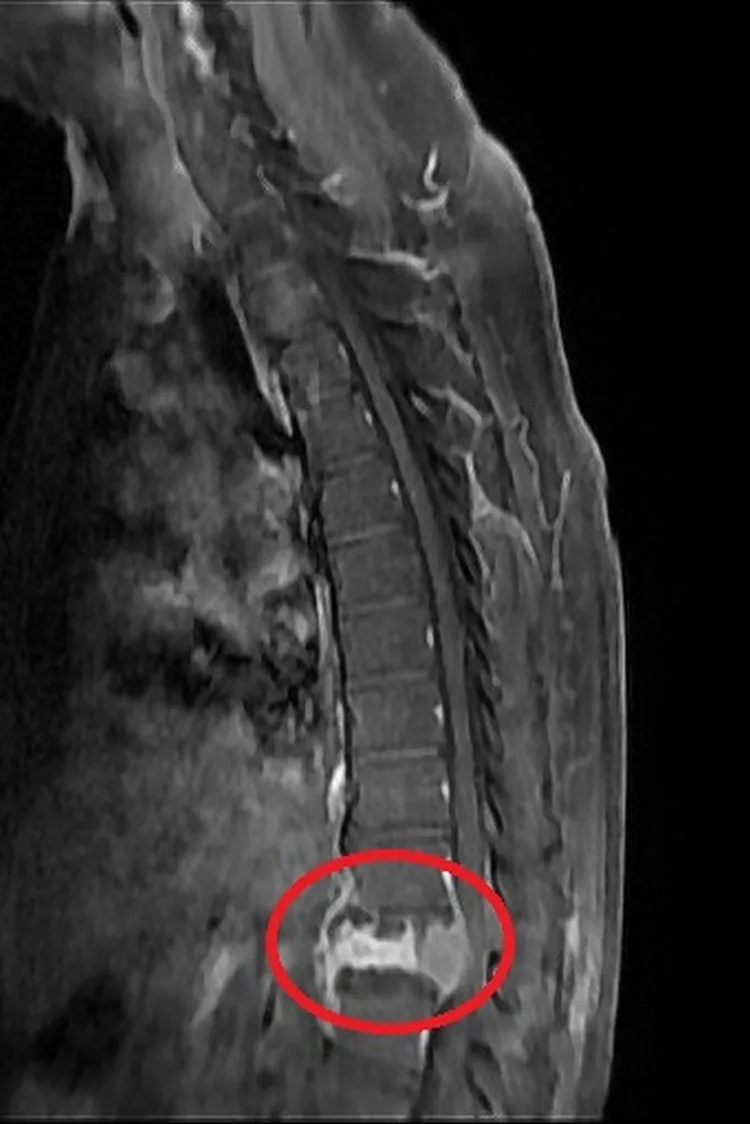

術前核磁共振顯示,第12節胸椎因腫瘤骨轉移而塌陷壓迫到神經管(左);透過減壓及微創釘手術,將4根微創骨釘分別固定在胸椎第11節及腰椎第1節,達到穩定脊椎的作用,此為術後X光。台北慈濟醫院提供